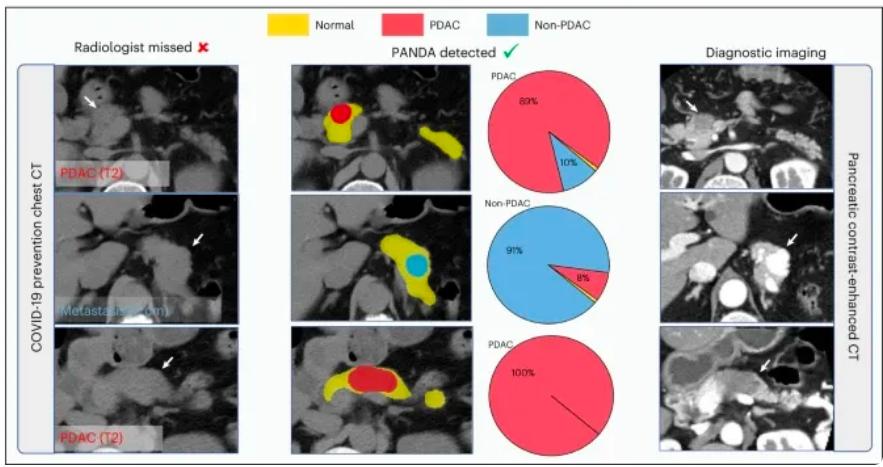

在前面提到的阿里所使用的PANDA模型中,最重要的一个技术,就是一种叫做“图像配准”的技术,将对比增强CT上的病变标注“复制”到非对比CT图像上。

用直观的语言来描述,这种做法就是:先找两张CT图片,其中一张是普通CT,另一张是增强CT,之后,PANDA通过将两张CT“重叠”在一起的办法,来将增强CT上的病变区域准确地映射到普通CT的相应位置上。

需要说明的是,这里的“重叠”,并不是简单地将两张图片进行物理上的重叠,而是通过算法,识别两张图片中的特征,并计算出它们之间的对应关系。

具体来说,在第一阶段,PANDA会使用nnU-Net模型——一种特定的深度学习架构,精确地识别和分割出胰腺的区域。就相当于用画笔勾勒出胰腺的轮廓。

在第二阶段,一旦胰腺区域被定位和分割出来,PANDA的联合分割和分类网络,就会判断这些区域是异常的还是正常的,如果异常,就要找出相应的病变区域。

第三阶段(Stage 3)- 病变亚型分类:在检测到病变之后,这个阶段的目标是对这些病变进行更细致的分类,比如区分不同类型的肿瘤或病变。